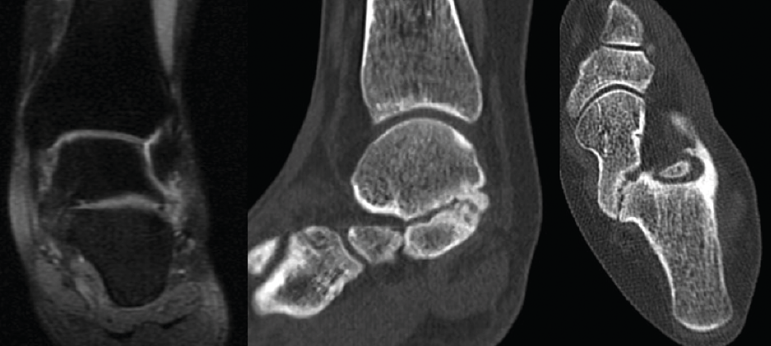

Figura 3. Confirmación de la coalición por resonancia magnética nuclear y tomografía axial computarizada.

Se trata de una paciente mujer de 27 años de edad, auxiliar sanitaria, con antecedentes de asma, depresión y psoriasis, que presenta un pie izquierdo plano valgo doloroso de 24° de valgo talar, por sinostosis calcaneoastragalina posterior. Dicha paciente presentaba una clínica de dolor en el seno del tarso y los tendones peroneos laterales. Como pruebas complementarias, se realizaron radiografías en carga de los pies y los tobillos, TAC y RMN del tobillo afecto. Se diagnostica de coalición tarsal de tipo 3 de la clasificación de Rozansky(26). Las articulaciones tibioperoneoastragalina y subtalar están preservadas clínica y radiológicamente. El balance articular es de: flexión = 45°; extensión = 15°; inversión = 5°; eversión = 0°. La escala de la American Orthopaedic Foot and Ankle Society (AOFAS) para el tobillo izquierdo presentaba un valor de 60 (20-35-5). Los ángulos radiológicos iniciales son: Moreau-Costa-Bartani interno = 143°; declinación talar = 25,8°; Meary = 9,9°; Kite = 25,5°; taloescafoideo = 54,6° (Tabla 1).

Se trata de una paciente mujer de 18 años de edad, higienista dental, sin antecedentes patológicos de interés, que presenta pies planos valgos bilaterales dolorosos, el derecho de 23° y el izquierdo de 21° de valgo, por sinostosis calcaneoastragalina media en ambos pies. En ella observamos básicamente una clínica de dolor en el seno del tarso, con déficit de movilidad de la articulación subtalar en ambos pies. Se realiza estudio mediante radiografías de los pies y los tobillos en carga y TAC de ambos pies (afectación bilateral). Radiológicamente, las articulaciones tibioperoneoastragalina y subtalar están preservadas. Se diagnostica de coalición tarsal de tipo 4 de la clasificación de Rozansky(26). El balance articular es de: flexión = 45°; extensión = 20°; inversión = 0°; eversión = 0°. La escala de la AOFAS para el tobillo derecho presentaba una puntuación de 62 (20-37-5). Los ángulos radiológicos iniciales son: Moreau-Costa-Bartani interno = 141°; declinación talar = 18,4°; Meary = 6,3°; Kite = 25,6°; taloescafoideo = 48,3°.